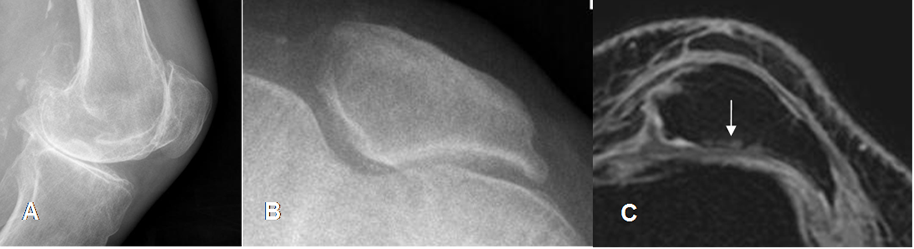

Fig 165 A. Inestabilidad patelar transversal.

A: Rx lateral y B: Rx tangencial. Cambios degenerativos con disminución del espacio patelofemoral, esclerosis y formación de osteofitos.

C: RM axial en 3D T1 STIR. Lateralización, pérdida del cartílago articular en la parte externa y lesiones osteocondrales, por Condromalacia GIV.